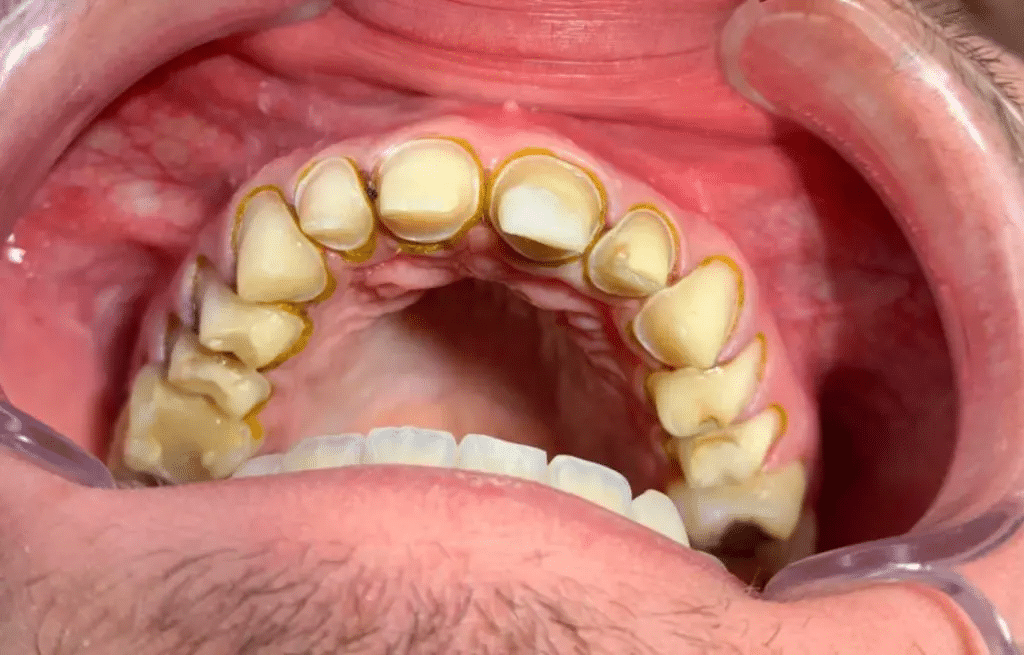

Treća posjeta – proba cirkona

U ovoj posjeti vršimo probu full anatomic cut back cirkonskih krunica bez glazure. Provjeravamo rubno zaptivanje krunica, tj. gledamo da li krunica čitavim obimom naliježe na stepenik zbrušenog zuba. Debljina ruba cirkonske krunice ne smije biti deblja od samog stepenika zbrušenog zuba tako da se pri prelasku sondom sa kruničnog na zubni dio ne osjeti otpor (“zapinjanje sonde”). Nakon što smo provjerili odnos zub/krunica pristupimo provjeravanju i eventualnoj artikulaciji zagriza. U ovoj posjeti pacijent prvi put vidi izgled svog budućeg osmijeha. Nakon zajedničkog analiziranja oblika boje i veličine zuba evidentiramo eventualne potrebne korekcije po želji pacijenta. Nakon toga slikamo pacijenta sa i bez ekartera iz različitih uglova. Ove fotografije koristmo za internu upotrebu da bi zajedno sa kolegama iz laboratorija dizajnirali finalni izgled “Hollywood smile” osmijeha.